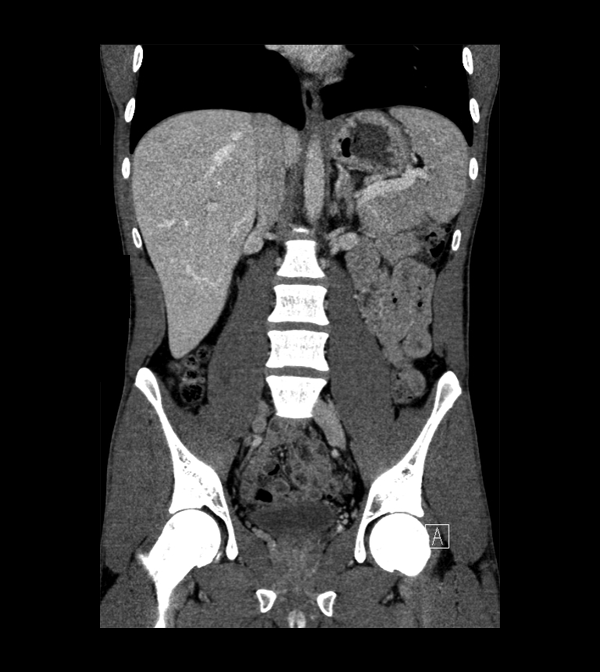

Body

Covers abdominal CT anatomy.